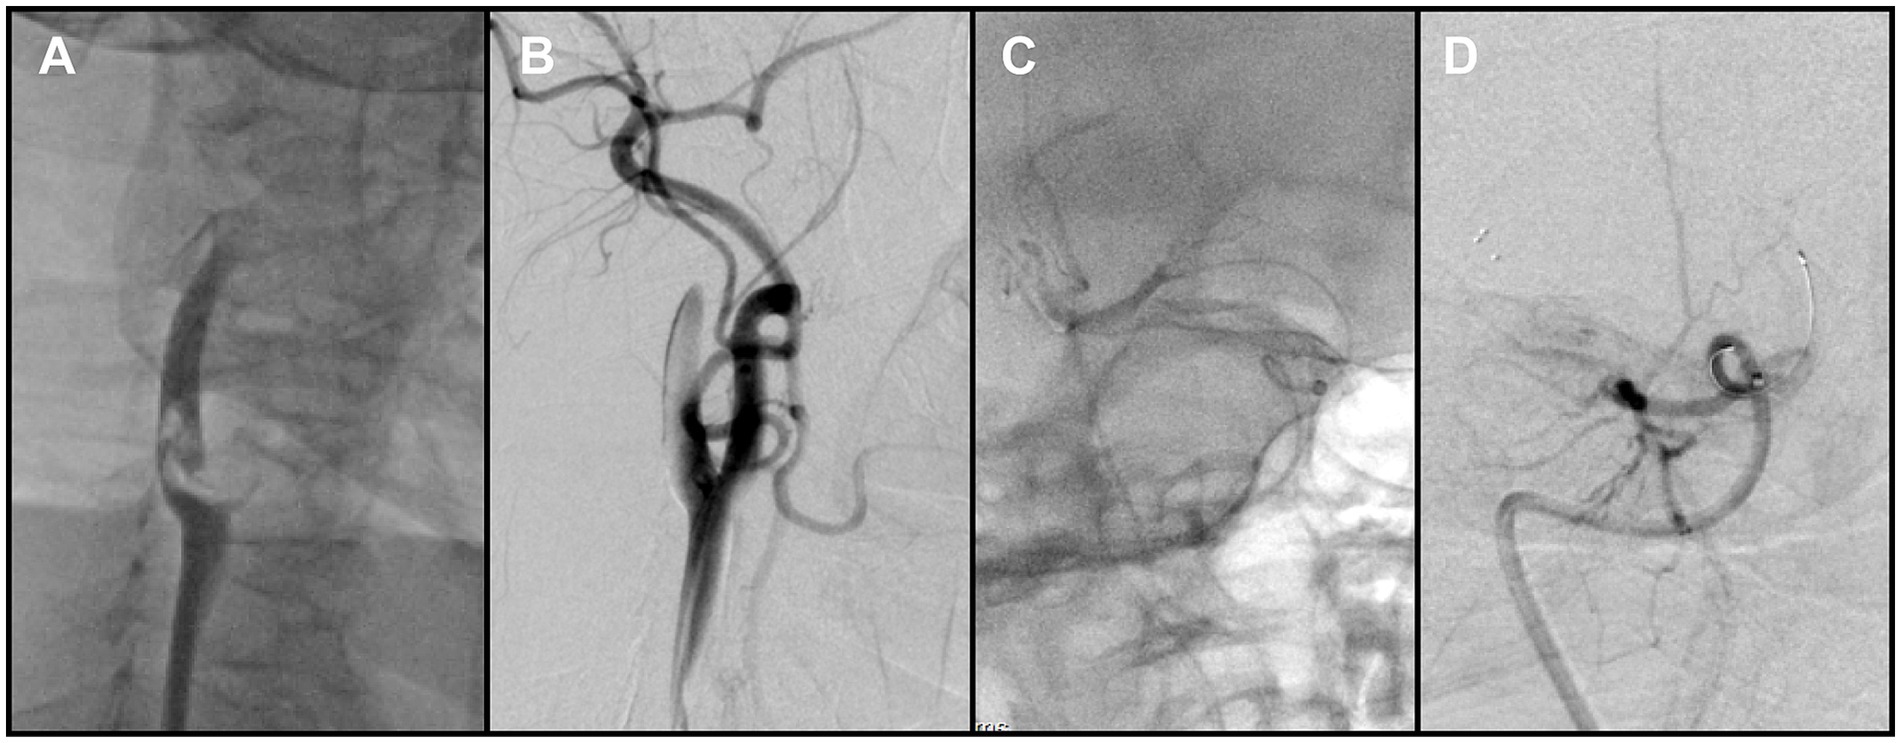

The Neuron MAX catheter was then advanced into the distal right CCA near the bifurcation. Before performing a complete diagnostic angiogram, a contrast injection was used to confirm catheter position. At this point, a large FFT was identified at the carotid bifurcation, involving into the origins of both the ICA and the ECA. The thrombus exhibited pulsatile motion synchronous with the cardiac cycle, consistent with a mobile/mural thrombus (Figure 2A). At the same time, antegrade flow in the ICA was stagnant, suggesting distal ICA occlusion. The overall presentation was therefore consistent with a tandem embolic lesion in the anterior circulation. Given the presence of collateral circulation, a proximal-to-distal treatment strategy was adopted.

Figure 2. (A) Right carotid angiography revealed a free-floating thrombus at the carotid bifurcation. (B) Following removal of the proximal thrombus, angiography showed persistent non-opacification of the distal right internal carotid artery (ICA). (C) Contrast injection after crossing of the occluded segment by the microcatheter delineated the distal vessel. (D) Post-stent deployment angiography demonstrated absence of antegrade flow across the occluded segment.

Aspiration thrombectomy was attempted through the Neuron MAX catheter, but resistance was encountered, suggesting catheter-tip or intraluminal clot occlusion. Continuous and pulsed aspiration failed to restore flow, and blind catheter withdrawal was avoided due to the risk of embolic escape. Therefore, a Solitaire 4 × 20 mm stent retriever (Medtronic, USA) was deployed at the tip of the Neuron MAX guiding catheter. With continuous aspiration applied through the guiding catheter, the stent was used to scrape and engage the obstructing thrombus. This maneuver was repeated three times, after which the guiding catheter was successfully cleared and patency restored. Subsequent angiography demonstrated complete removal of the thrombus at the bifurcation of the right internal carotid artery (Figure 2B).

2.3 Intracranial flow restoration and proximal lesion

After restoration of catheter patency, the Neuron MAX catheter was navigated into the ICA. A Catalyst 6 aspiration catheter (Stryker Neurovascular, USA) was advanced and used to aspirate thrombotic material from segments C1 through C4 of the right ICA, with adequate backflow but no significant thrombus was retrieved. The microcatheter and microwire were then used to traverse the terminal ICA occlusion and advance into the distal M1 segment (Figure 2C). Following deployment of the Solitaire stent retriever, angiography still showed no antegrade flow (Figure 2D). Because of the heavy thrombus burden, a combined approach was adopted, retrieving the stent retriever together with en bloc withdrawal of the aspiration catheter.